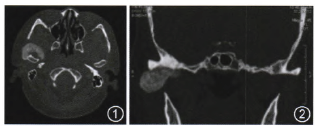

CT:右顳下頜關(guān)節(jié)有一不規(guī)則鈣化高密度灶,呈啞鈴形。外側(cè)部分類似球形,突破關(guān)節(jié)腔位于顴弓下方、乙狀切跡外側(cè)及髁突前方;中間部分沿關(guān)節(jié)腔分布,呈盤狀,與關(guān)節(jié)面間有潛在間隙,患例關(guān)節(jié)腔較健側(cè)明顯增寬;內(nèi)側(cè)部分跨越關(guān)節(jié)結(jié)節(jié)向前內(nèi)斜形進(jìn)入顳骨鱗部和蝶骨巖部,顱底骨質(zhì)破壞(圖1~3)。

圖1CT可見病灶突出關(guān)節(jié)腔內(nèi)外側(cè)呈球狀生長;圖2顳下頜關(guān)節(jié)間隙不均一的高密度盤狀鈣化影,鈣化影與髁突之間可見潛在間隙,病灶沿關(guān)節(jié)間隙分布,并向間隙內(nèi)及外突出;圖3病灶向前內(nèi)突出至顳下窩.鈣化物超越關(guān)節(jié)腔向外突出至面部,向內(nèi)擴(kuò)展至顱底;